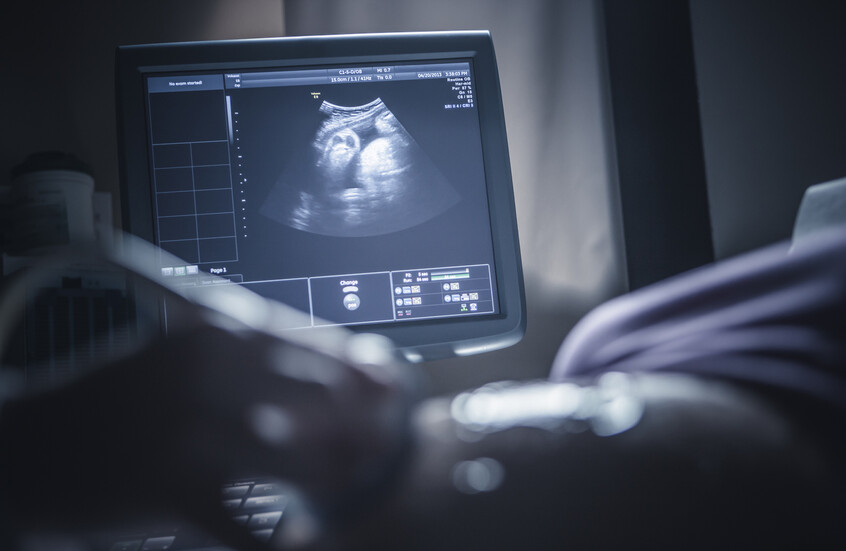

واعتمدت الدراسة على متابعة مجموعة من الحوامل في ثلاثة مستشفيات كبرى في برشلونة، وخضع 132 طفلا حديث الولادة لفحوصات متقدمة بالرنين المغناطيسي خلال الشهر الأول لتقييم مستوى نضج أدمغتهم عبر قياس تقدم عملية الميالينة.